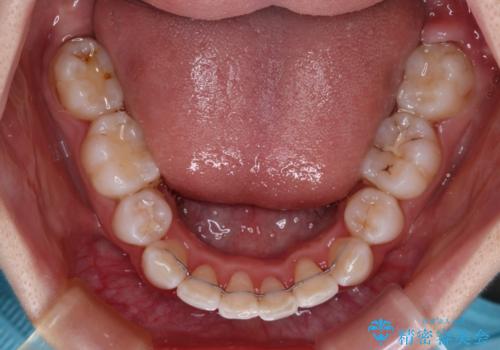

叢生・ディープバイト・突出 ワイヤー装置での抜歯矯正で全てを解決

下顎前歯が隠れるほどのディープバイトであり、それによる顎の負担も大きかったため、ディープバイトもしっかりと改善できるよう、表側のワイヤー装置にて矯正治療を行うこととしました。

ディープバイトは、治療を行っていた我々も驚くほど、短期間で劇的に改善することができました。